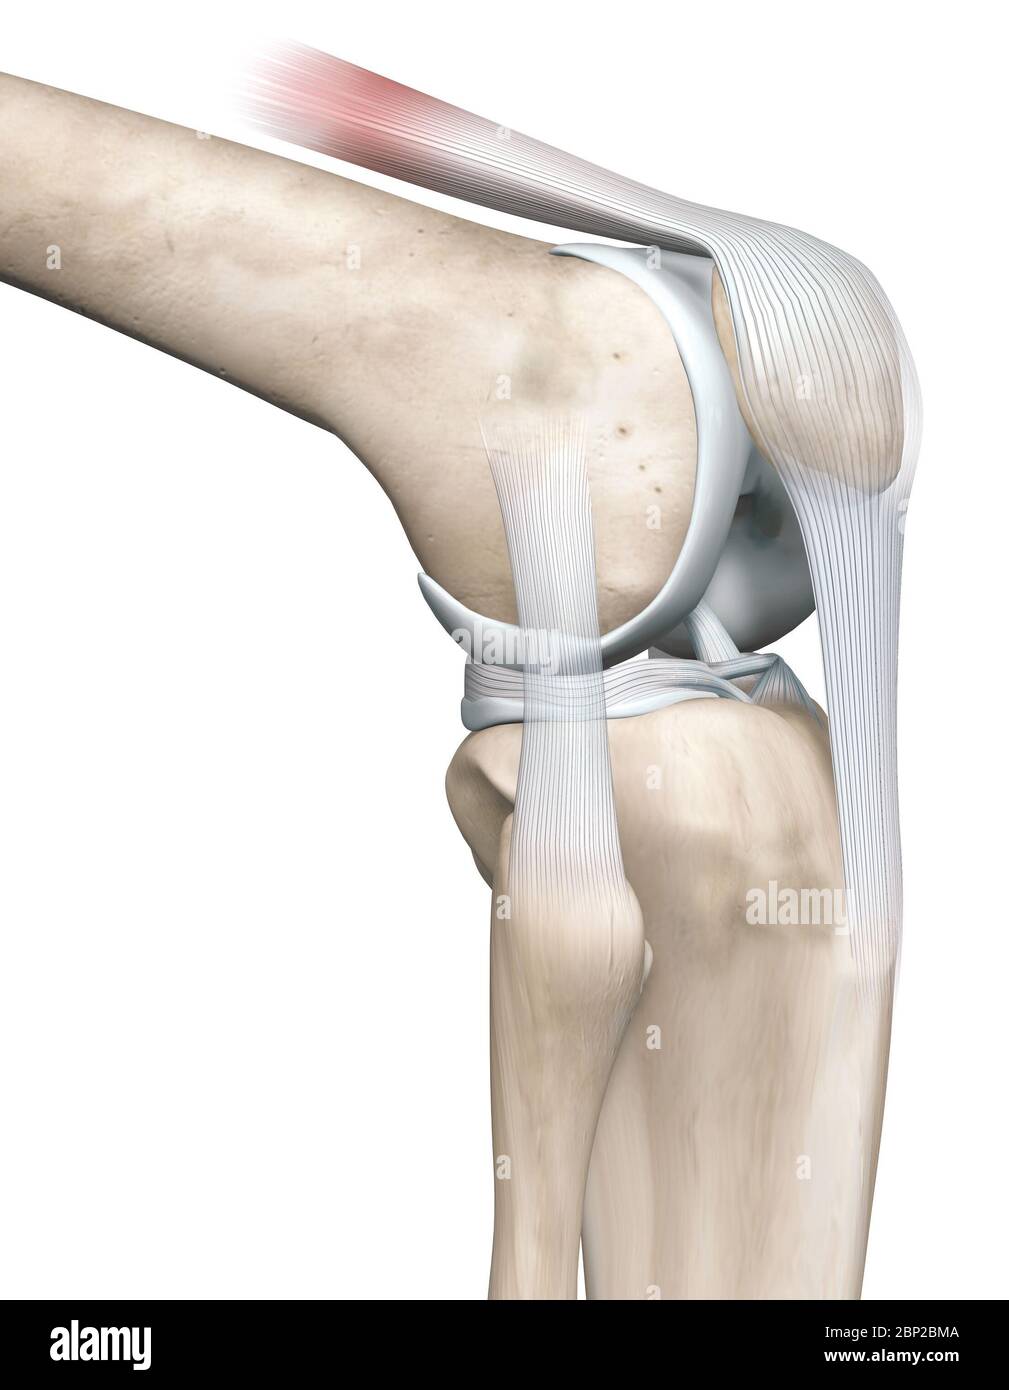

3D illustration showing knee joint with femur, fibula and articular capsule, menisci and ligaments Stock Photohttps://www.alamy.com/image-license-details/?v=1https://www.alamy.com/3d-illustration-showing-knee-joint-with-femur-fibula-and-articular-capsule-menisci-and-ligaments-image357782890.html

3D illustration showing knee joint with femur, fibula and articular capsule, menisci and ligaments Stock Photohttps://www.alamy.com/image-license-details/?v=1https://www.alamy.com/3d-illustration-showing-knee-joint-with-femur-fibula-and-articular-capsule-menisci-and-ligaments-image357782890.htmlRF2BP2BMA–3D illustration showing knee joint with femur, fibula and articular capsule, menisci and ligaments

3D illustration showing knee joint with transparent femur and articular capsule, menisci and ligaments Stock Photohttps://www.alamy.com/image-license-details/?v=1https://www.alamy.com/3d-illustration-showing-knee-joint-with-transparent-femur-and-articular-capsule-menisci-and-ligaments-image357783032.html

3D illustration showing knee joint with transparent femur and articular capsule, menisci and ligaments Stock Photohttps://www.alamy.com/image-license-details/?v=1https://www.alamy.com/3d-illustration-showing-knee-joint-with-transparent-femur-and-articular-capsule-menisci-and-ligaments-image357783032.htmlRF2BP2BWC–3D illustration showing knee joint with transparent femur and articular capsule, menisci and ligaments

3D illustration showing knee joint with transparent femur and articular capsule, menisci and ligaments Stock Photohttps://www.alamy.com/image-license-details/?v=1https://www.alamy.com/3d-illustration-showing-knee-joint-with-transparent-femur-and-articular-capsule-menisci-and-ligaments-image357783041.html

3D illustration showing knee joint with transparent femur and articular capsule, menisci and ligaments Stock Photohttps://www.alamy.com/image-license-details/?v=1https://www.alamy.com/3d-illustration-showing-knee-joint-with-transparent-femur-and-articular-capsule-menisci-and-ligaments-image357783041.htmlRF2BP2BWN–3D illustration showing knee joint with transparent femur and articular capsule, menisci and ligaments

3D illustration showing knee joint with transparent femur and articular capsule, menisci and ligaments Stock Photohttps://www.alamy.com/image-license-details/?v=1https://www.alamy.com/3d-illustration-showing-knee-joint-with-transparent-femur-and-articular-capsule-menisci-and-ligaments-image357782791.html

3D illustration showing knee joint with transparent femur and articular capsule, menisci and ligaments Stock Photohttps://www.alamy.com/image-license-details/?v=1https://www.alamy.com/3d-illustration-showing-knee-joint-with-transparent-femur-and-articular-capsule-menisci-and-ligaments-image357782791.htmlRF2BP2BGR–3D illustration showing knee joint with transparent femur and articular capsule, menisci and ligaments